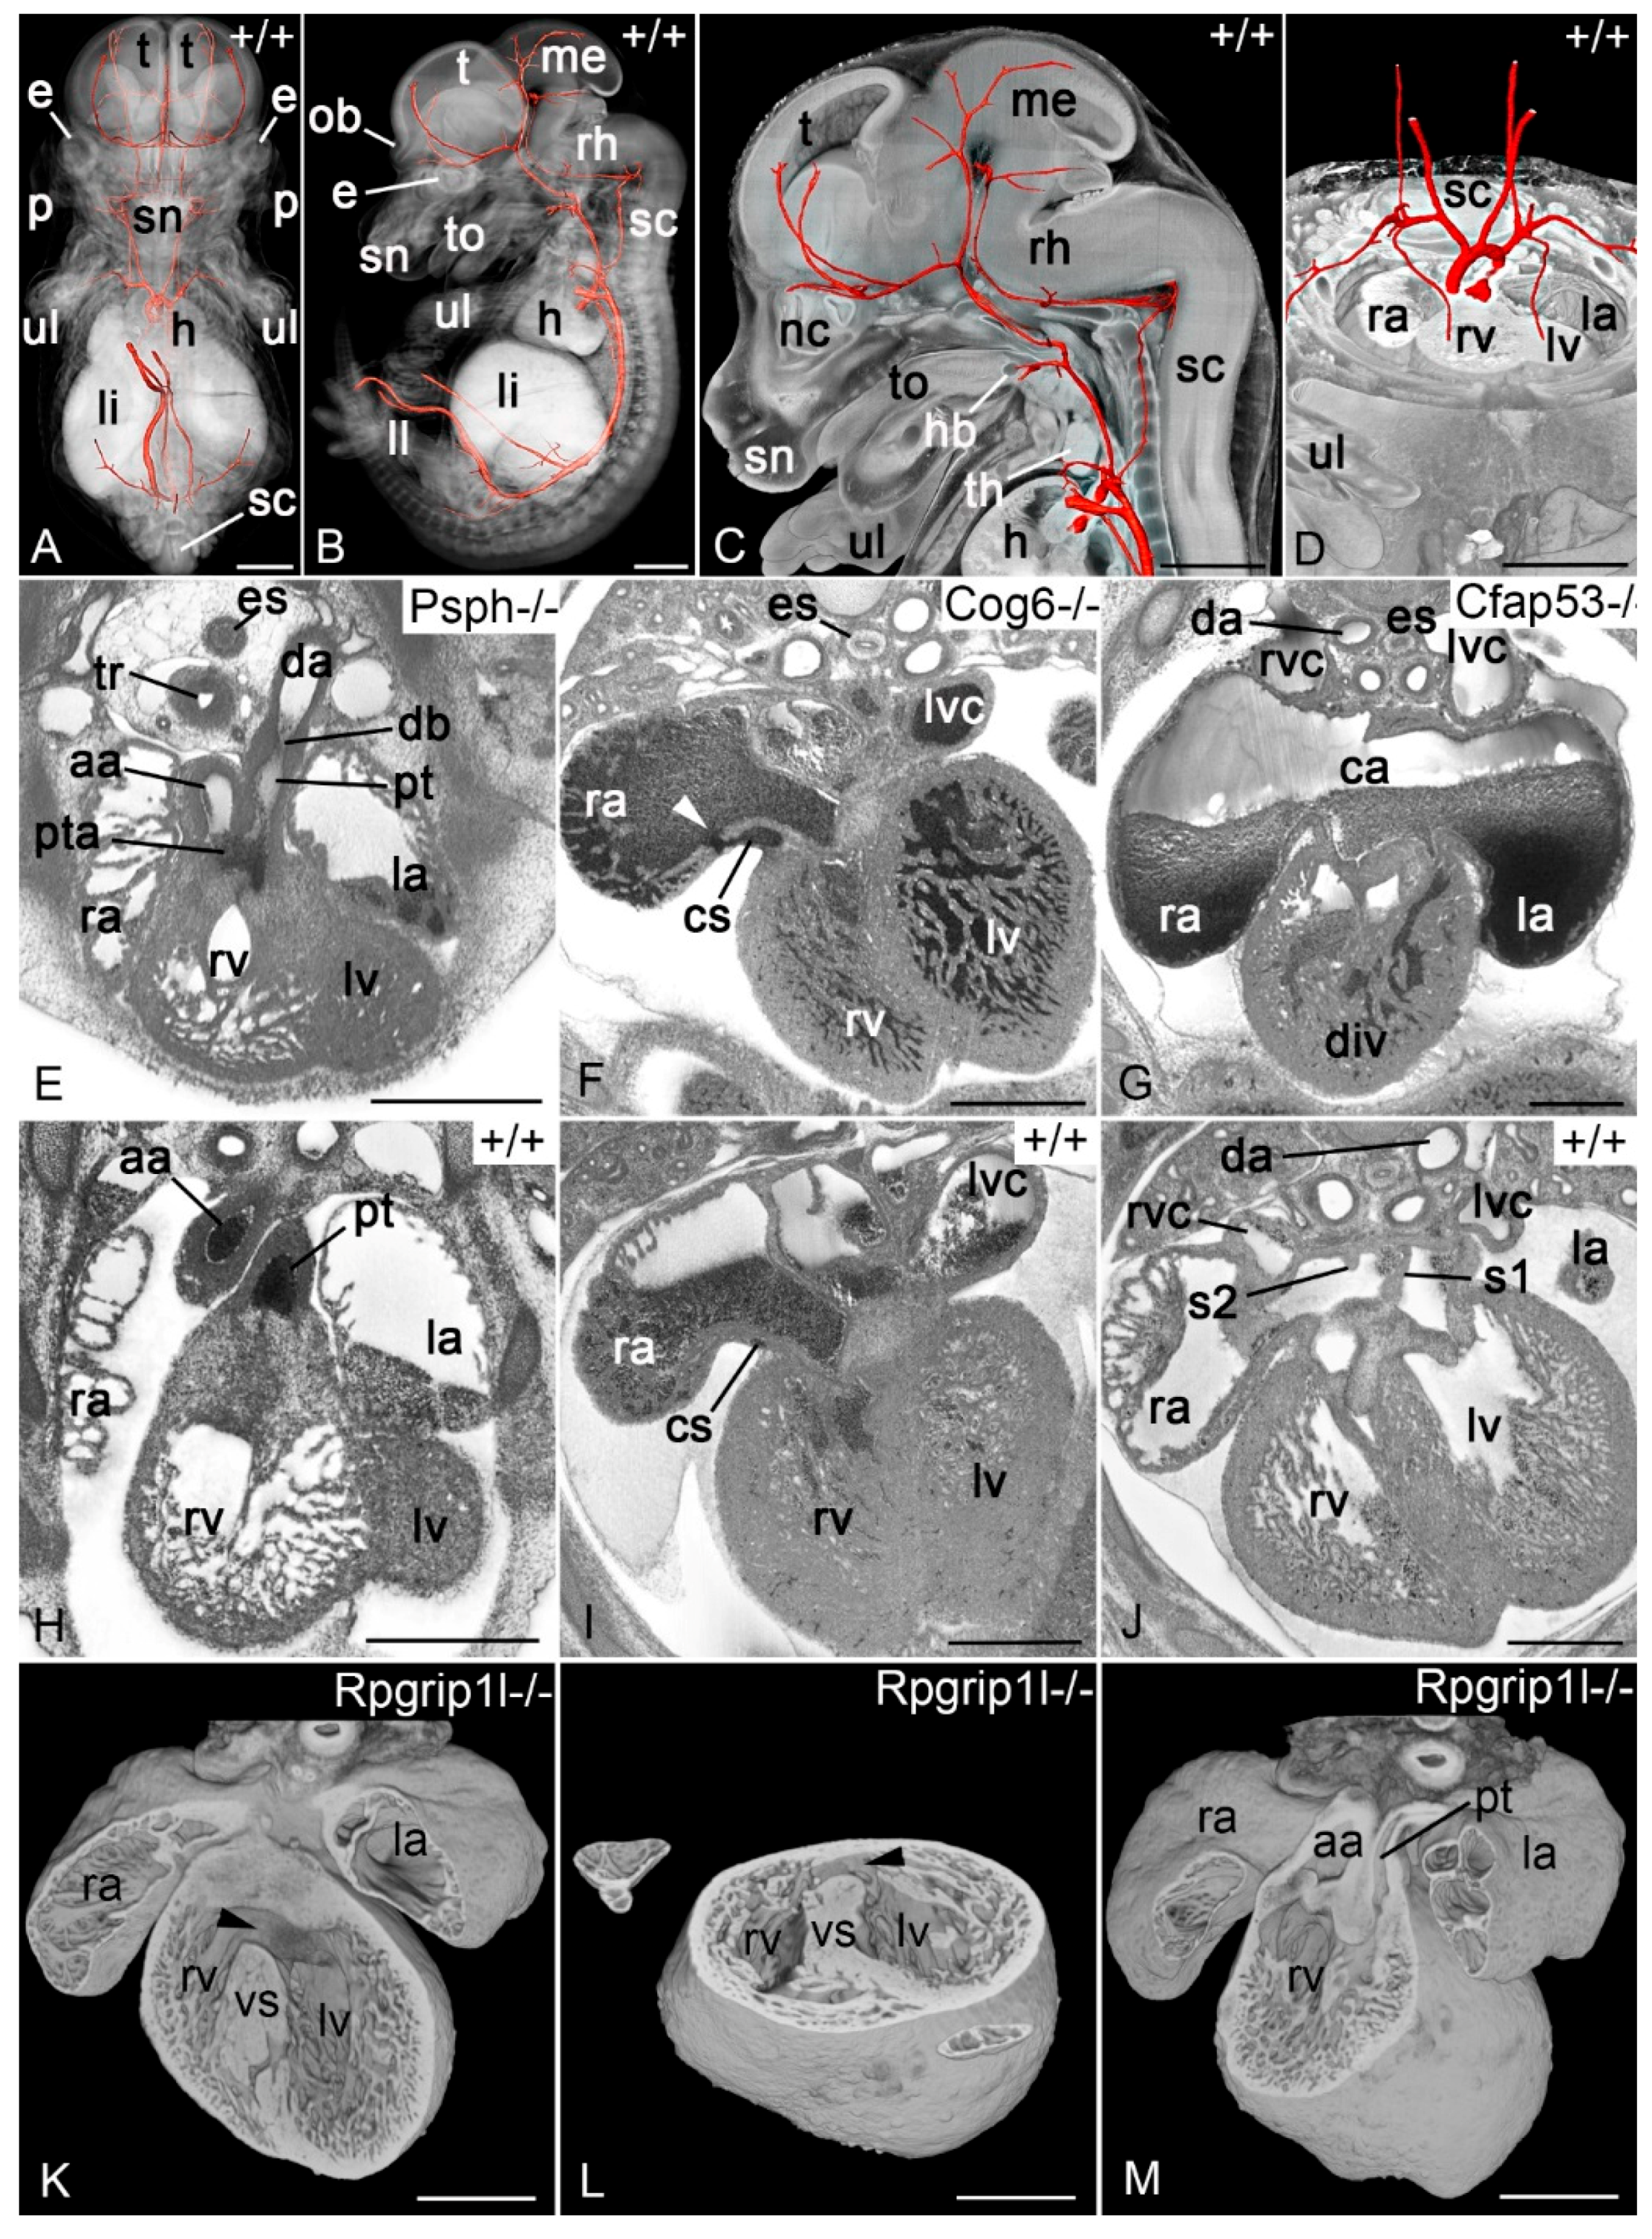

3.2. Biomedical Model Organisms

3.2.1. Zebrafish and Frog Embryos

3.2.2. Chick Embryos

3.2.3. Mouse Embryos

- Weninger, W.J.; Geyer, S.H.; Martineau, A.; Galli, A.; Adams, D.J.; Wilson, R.; Mohun, T.J. Phenotyping structural abnormalities in mouse embryos using high-resolution episcopic microscopy. Dis Model. Mech. 2014, 7, 1143–1152. [Google Scholar] [CrossRef] [PubMed] [Green Version]

- Wilson, R.; McGuire, C.; Mohun, T.; Adams, D.; Baldock, R.; Bhattacharya, S.; Collins, J.; Fineberg, E.; Firminger, L.; Galli, A.; et al. Deciphering the mechanisms of developmental disorders: Phenotype analysis of embryos from mutant mouse lines. Nucleic Acids Research 2016, 44, D855–D861. [Google Scholar] [CrossRef] [PubMed]

- Wilson, R.; Geyer, S.H.; Reissig, L.; Rose, J.; Szumska, D.; Hardman, E.; Prin, F.; McGuire, C.; Ramirez-Solis, R.; White, J.; et al. Highly variable penetrance of abnormal phenotypes in embryonic lethal knockout mice. Wellcome. Open Res. 2016, 1, 1. [Google Scholar] [CrossRef] [PubMed] [Green Version]

- Geyer, S.H.; Reissig, L.F.; Husemann, M.; Hofle, C.; Wilson, R.; Prin, F.; Szumska, D.; Galli, A.; Adams, D.J.; White, J.; et al. Morphology, topology and dimensions of the heart and arteries of genetically normal and mutant mouse embryos at stages S21–S23. J. Anat. 2017, 231, 600–614. [Google Scholar] [CrossRef] [PubMed]